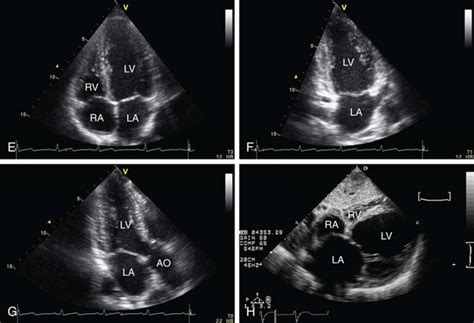

Apical Views

The apical views are obtained by placing the transducer at the apex of the heart, typically in the fifth intercostal space along the midclavicular line. These views are excellent for assessing the left ventricular apex, mitral valve, and left atrium. The apical four-chamber view provides a comprehensive image of all four chambers of the heart, allowing for evaluation of chamber size, wall thickness, and valve function. This view is particularly useful for assessing mitral and tricuspid regurgitation, as well as detecting atrial and ventricular septal defects. Common pathologies identified in the apical four-chamber view include dilated cardiomyopathy, hypertrophic cardiomyopathy, atrial fibrillation, and congenital heart defects. The apical two-chamber view is obtained by rotating the transducer from the apical four-chamber view, aligning it with the left ventricle and left atrium. This view is ideal for assessing left ventricular regional wall motion and evaluating mitral valve stenosis or regurgitation. The apical long-axis view, also known as the apical three-chamber view, is obtained by further rotating the transducer from the apical two-chamber view, bringing the aorta into view. This view provides a longitudinal image of the left ventricle, left atrium, and aorta, allowing for assessment of aortic valve function and detection of aortic aneurysms or dissections. The apical views are essential for a complete echocardiographic examination, providing valuable information about left ventricular function and valvular abnormalities. So, make sure you’re comfortable with these views and their anatomical landmarks!

Subcostal Views

The subcostal views are obtained by placing the transducer below the ribcage, typically in the epigastric region. These views are particularly useful when the parasternal and apical views are difficult to obtain due to body habitus or lung disease. The subcostal four-chamber view provides a similar image to the apical four-chamber view, allowing for evaluation of all four chambers of the heart. This view is especially helpful for assessing atrial and ventricular septal defects, as well as detecting pericardial effusions. The subcostal short-axis view provides a cross-sectional image of the left ventricle, similar to the parasternal short-axis view. This view is useful for assessing regional wall motion abnormalities and evaluating the right ventricle. The subcostal views are valuable tools for obtaining echocardiographic images in challenging patients, ensuring that a comprehensive cardiac assessment can be performed regardless of body size or lung condition. So, keep these views in your toolkit for those tough cases!